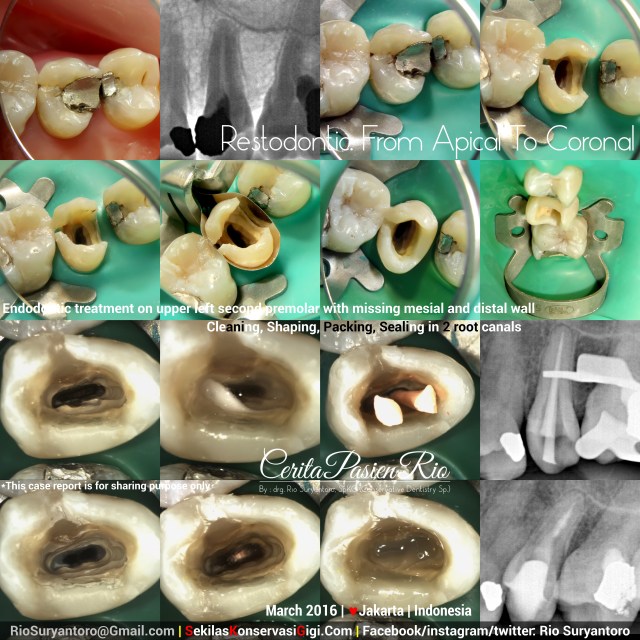

A patient came with a big cavity in his tooth, he said that this tooth had already treated by another operator for three visits but he didn’t know when to end the treatment.

Apical periodontitis on lower left second premolar with a partially broken temporary filling on class II cavity.

As usual, i did access preparation and started build up the missing wall. I used Z350XT (3M) composite resin with OmniMatrix (Ultradent). Cleaning and shaping was done with ProtaperNext (Dentsply) and Sodium Hypochlorite (NaOCl) 5,24%. Coronally sealed with low shrinkage stress flowable composite Filtek_Bulkfil (3M) and SDR (Dentsply). Xray evaluation taken with Durr Sensor 70kV, 3mA, 0,06 seconds..

This treatment still continue to build up the coronal layer with composite resin..